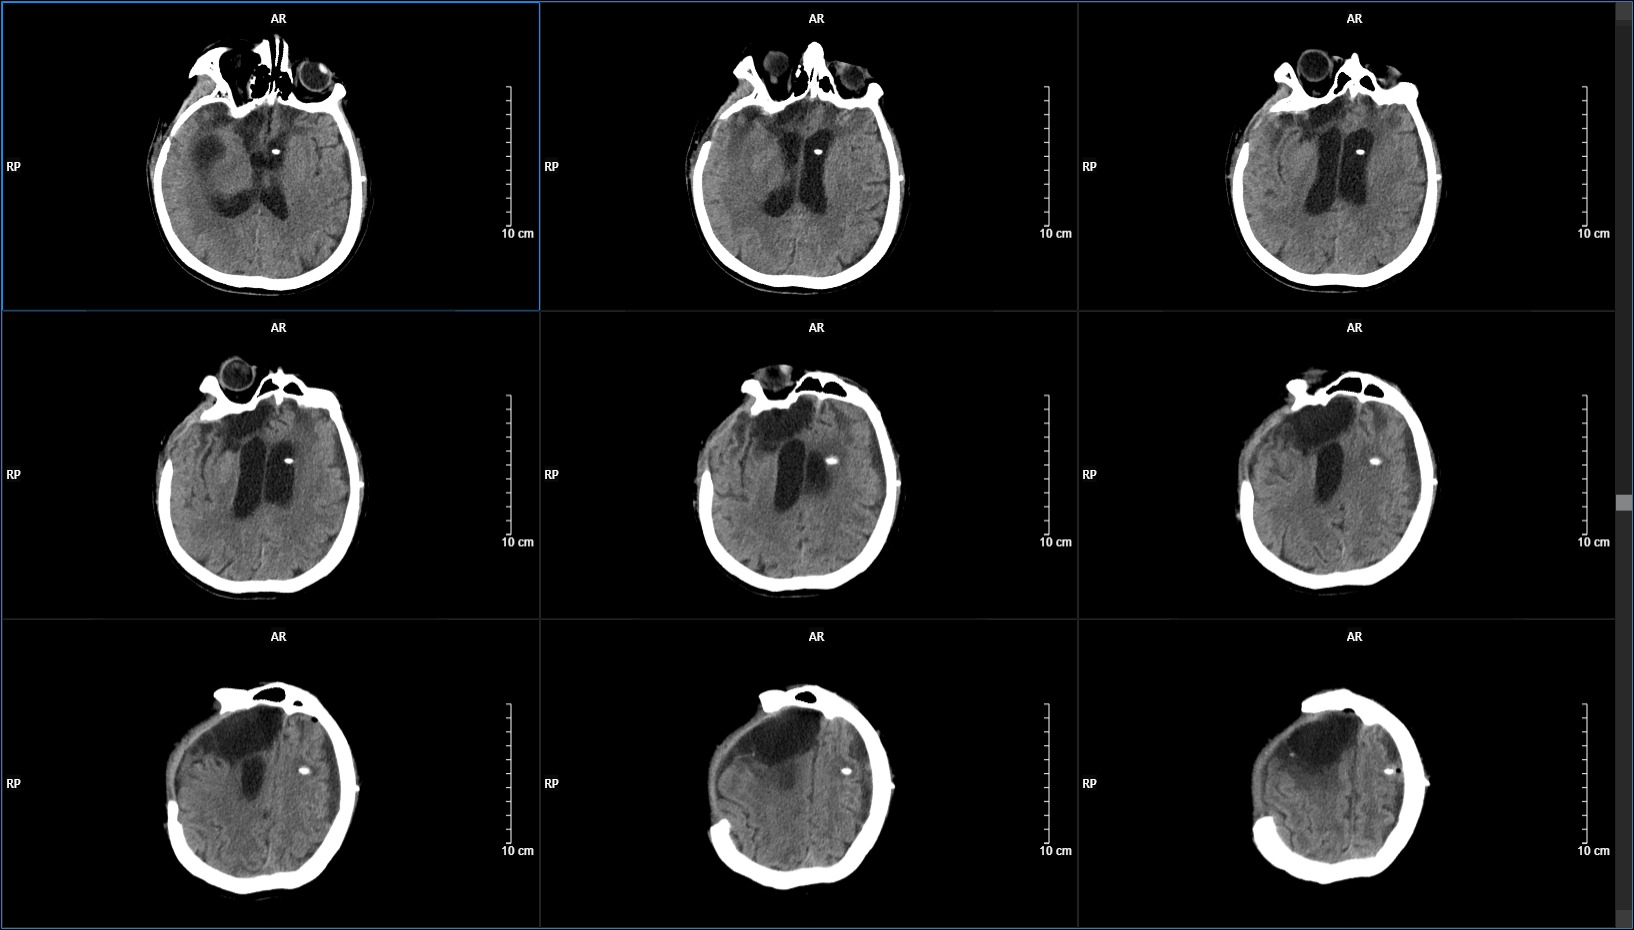

于分流术后20天,为更进一步治疗,决定行硬膜下积液清除+颅骨修补术。(术中见包膜完整,切除过程中过于追求全切导致术中损伤静脉,术后出现颞部梗死)。